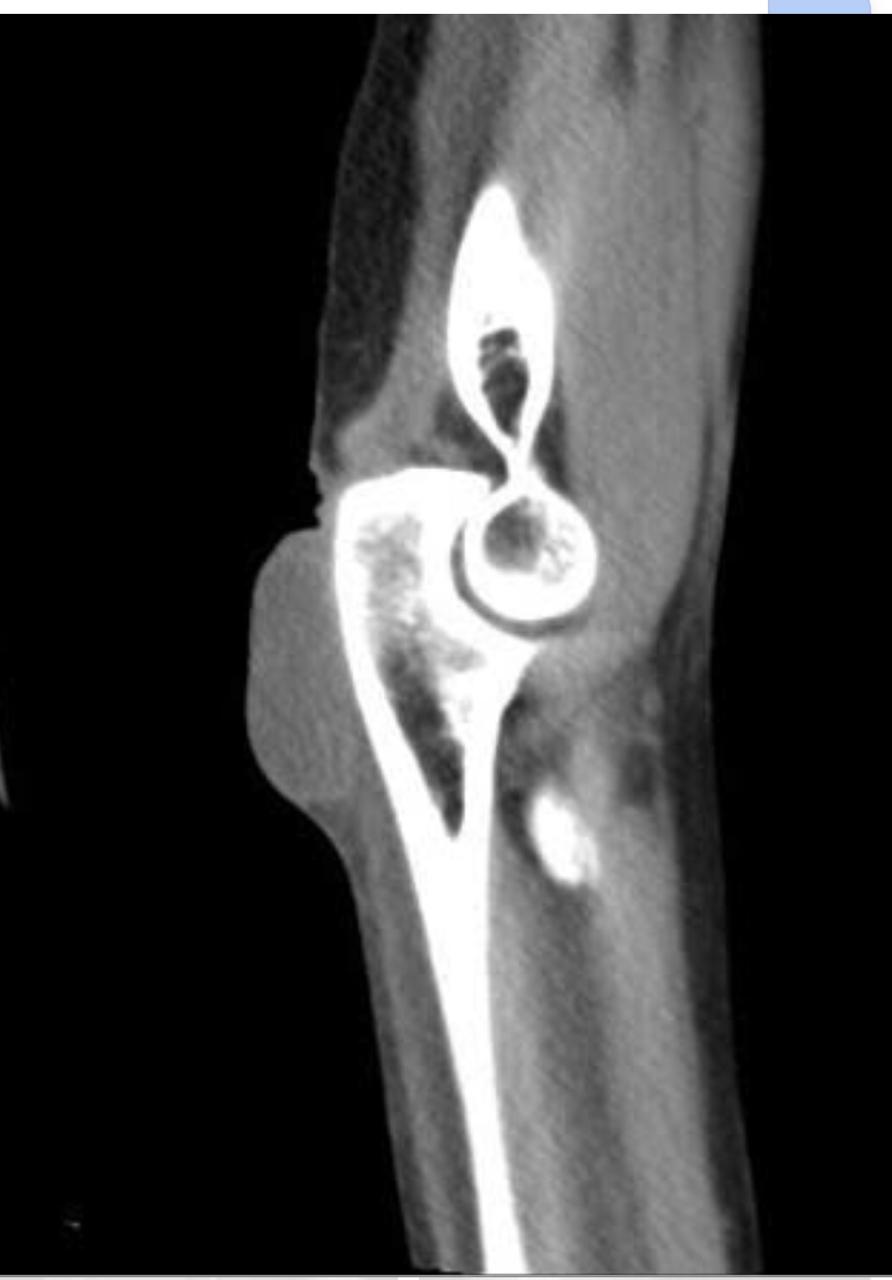

Olecranon bursitis refers to inflammation of the olecranon bursa. The olecranon bursa is a subcutaneous space lined with a synovial membrane that secretes fluid to provide smooth and almost frictionless motion between the skin, the subcutaneous tissues, and the olecranon. Because of its superficial location, it is a common site for injury, inflammation, and infection. Repeated traumatization of the elbows at work led to common terms for different forms of occupational bursitis such as “student's elbow” or “miner's elbow”.

Approximately one third of the cases of olecranon bursitis are septic. Many patients with septic olecranon bursitis lack a history of trauma or a visible injury over the olecranon.

Lateral radiograph of the elbow reveals soft tissue swelling superficial to the olecranon. Ultrasound may show a fluid collection in the olecranon bursa, features of synovial proliferation and/or hyperemia.

CT will show fluid density at the subcutaneous tissue superficial to the elbow. Bursal fluid collection in MRI has the following features: hypointense-T1, mainly hyperintense-T2, and enhancement of bursal margins in post contrast imaging.